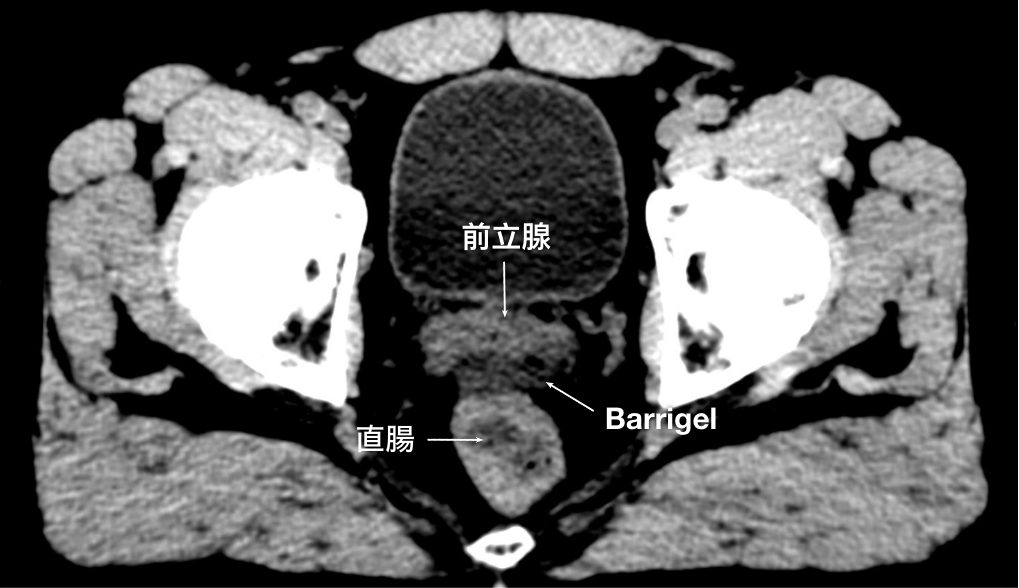

CT画像

CT画像提供:Suraj Singh, MD

Radiation Oncologist, Colorado, United States